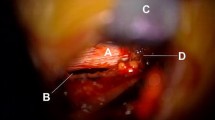

Neck muscle fatigue test

The Neck Muscle Fatigue Test consists of a sustained neck extension against a submaximal load measured with a handheld dynamometer at the occiput. For this test, the near-infrared spectroscopy (NIRS) will be performed using the PortaLite device (Artinis, Elst, Netherlands) to measure oxygen consumption in the neck skeletal muscles. HDEMG measurements will also be done during the fatigue test for the trapezius muscles only. All the 2D surface EMG grids from the previous tests shall be removed except of the grids placed on the trapezius muscle. The subject will be in sitting position and the NIRS sensors will be attached on the back of the subject’s neck with double-adhesive tape, one on each side on the paravertebral muscles above the level of C7 (Fig. 5a). Dark kinesiotape will be placed over the sensors to avoid artifacts from ambient light. The handheld dynamometer will be positioned at the occiput to monitor subject force output for targeting and feedback purposes. The measurements will be performed continuously before, during and after the neck muscle fatigue test. The NIRS sensors are connected via bluetooth to a laptop which will monitor the local muscle oxygen (StO2) in the tissue continuously.

a Placement of probes, b Image of example data trace. X-axis: time. Y-axis: local muscle oxygen saturation in percent. 1: Baseline values are recorded for 120 sec. 2: 2 minutes extension exercise. 3: Resting 10 seconds. 4: 2 minutes extension, 5: Recovery phase and hyperaemia (The images are original pictures taken by the team)

After 2 minutes with recording of the baseline value, the subject shall perform a neck muscle fatigue test, i.e. the participants shall extend isometrically the neck from neutral position against a submaximal load. If the participant feels fatigued but latest after 2 minutes, a resting period of 10 seconds is implemented and monitoring continued. The procedure shall be repeated one more time afterwards. After the second extension task, a 2 minutes resting period will be recorded (Fig. 5b).